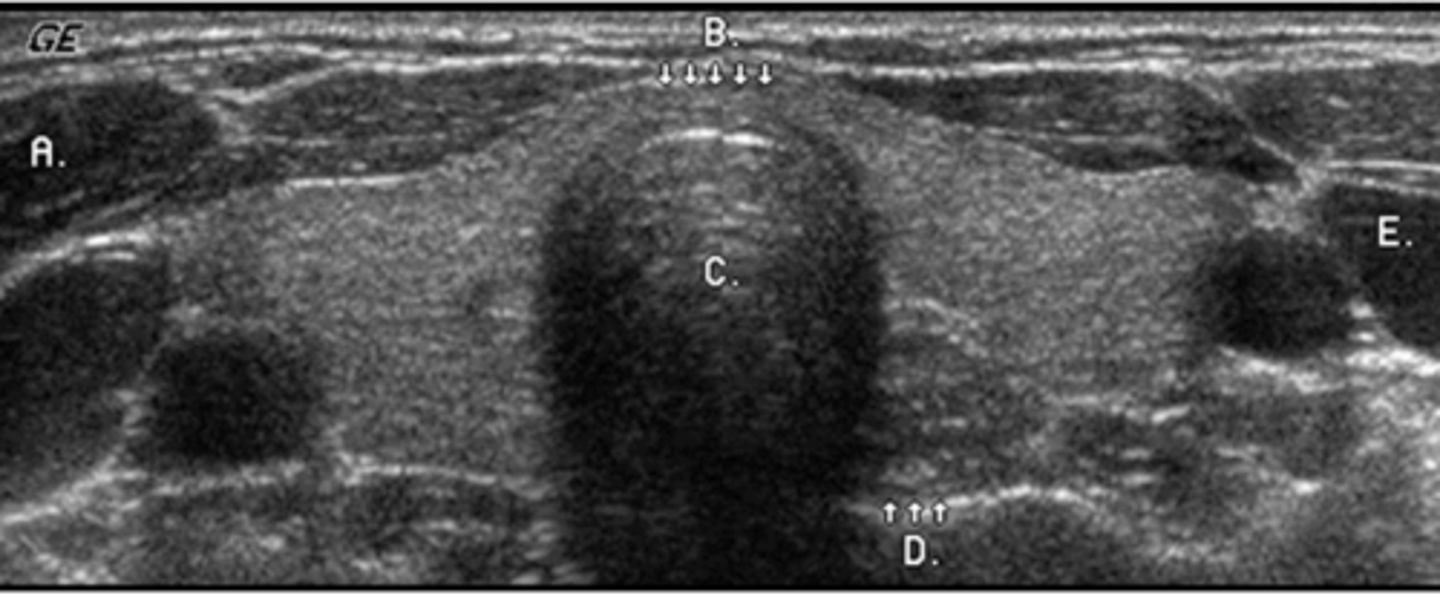

A 49-year-old male presented with a clinical history of liver cirrhosis and portal hypertension. In the transverse image below, multiple hypoechoic structures are seen at the splenic hilum and between the kidney and spleen. What is the most likely etiology of these structures.

a. multiple aneurysms of the splenic artery

b. splenic and retroperitoneal varices

c. loculated ascites

d. polycystic kidney disease

e. fluid-filled loops of bowel